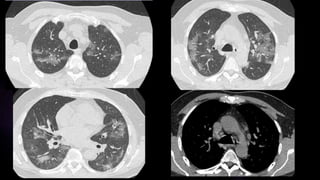

Lóbulo superior derecho: 50% (03 ptos)

Lóbulo medio derecho: 30% (03 ptos)

Lóbulo inferior derecho: 60% (04 ptos)

Lóbulo superior izquierdo: 60% (04 ptos)

Lóbulo inferior izquierdo: 80% (05 ptos)

Puntuación: 19 ptos

CONCLUSIÓN: AFECCIÓN SEVERA

CONCLUSIÓN: AFECCIÓN SEVERA –

CATEGORIA B (PATRÓN EMPEDRADO)